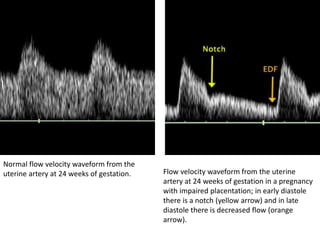

Normal flow velocity waveform from the

uterine artery at 24 weeks of gestation. Flow velocity waveform from the uterine

artery at 24 weeks of gestation in a pregnancy

with impaired placentation; in early diastole

there is a notch (yellow arrow) and in late

diastole there is decreased flow (orange

arrow).